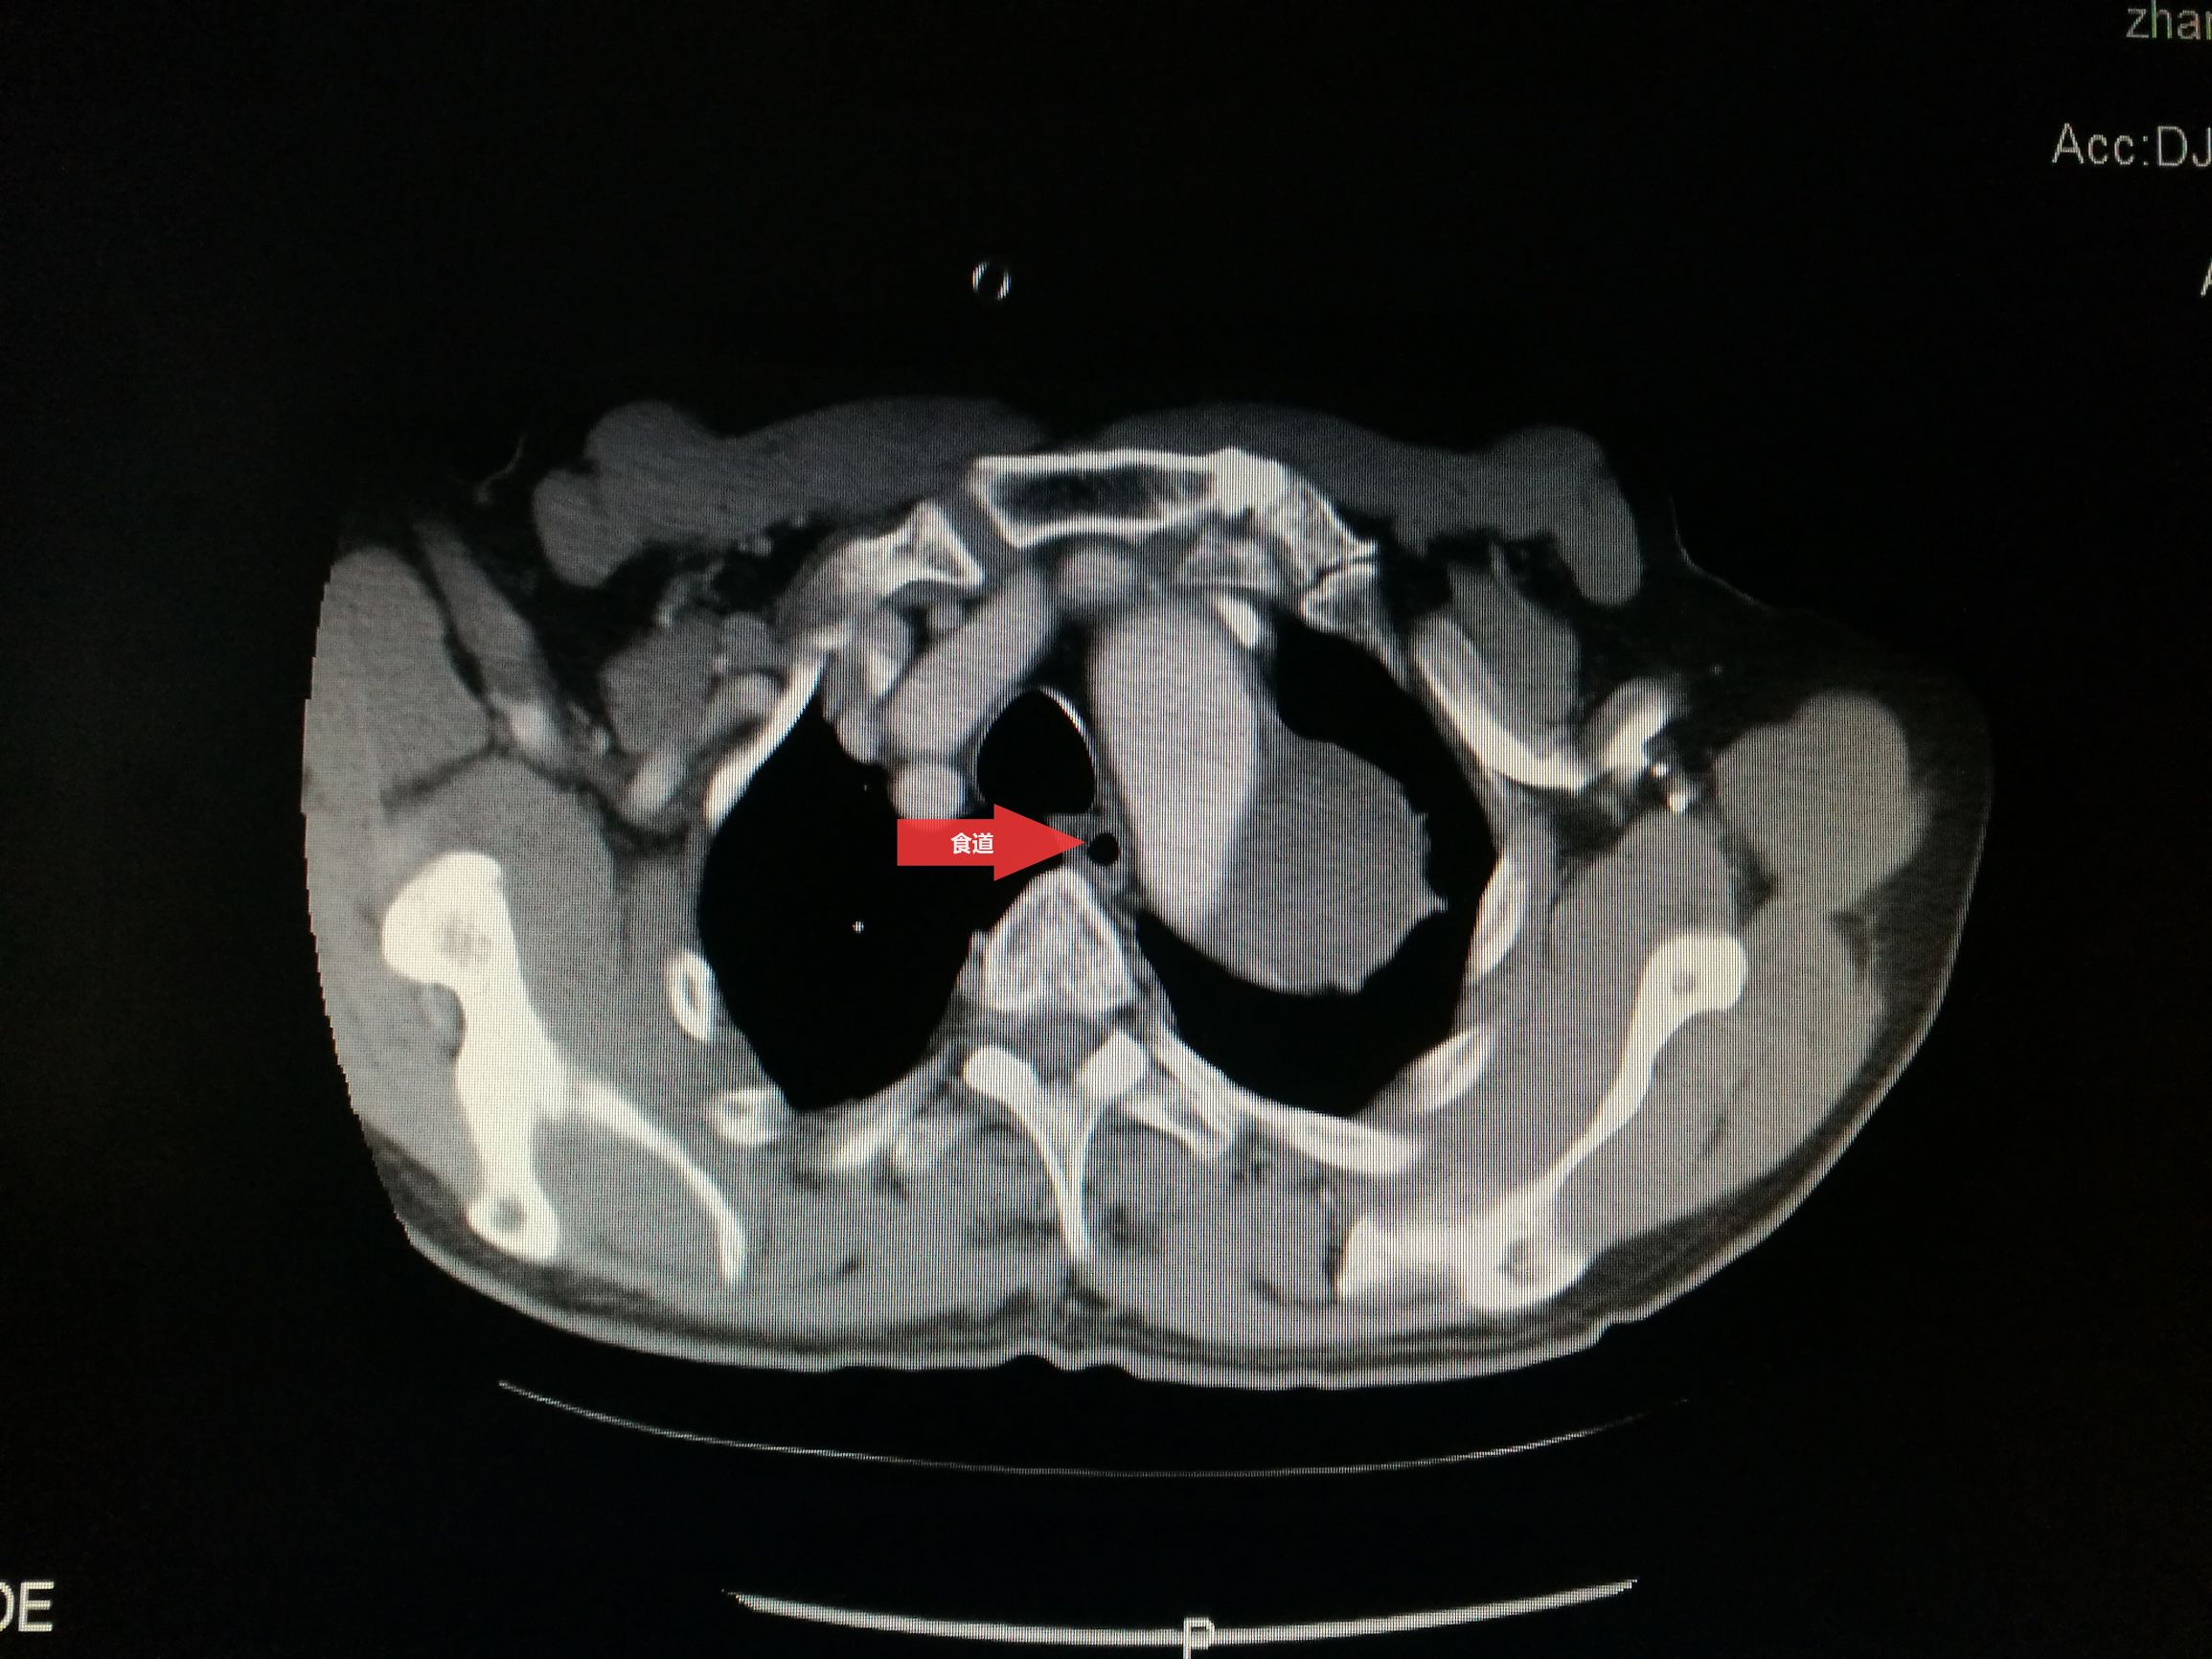

此例患者进行发病时未能确诊,进入慢性期后假腔扩张瘤样变。在CT的部分层面,食道受压看不到。重建影像可见假腔扩张,动脉扭曲。